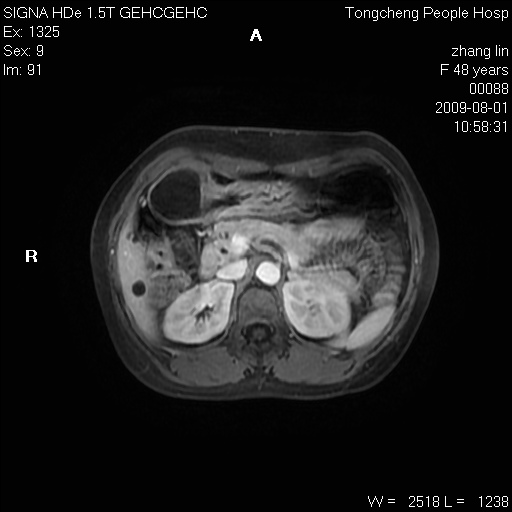

女,48岁。健康体检,彩超发现右肾占位性病变。平素健康。

临床诊断:右肾占位性病变,性质待定(囊肿?肿瘤?)。

上中腹部mr平扫+增强扫描,图像如下:

右肾上极见一类圆形病灶,t1wi呈等信号t2wi呈等高混杂信号,三期增强无强化,边界清---考虑囊肿出血。

同反相位均表现为等信号,病变无强化,考虑含蛋白的囊肿可能,弥散加权相或许有些帮助,